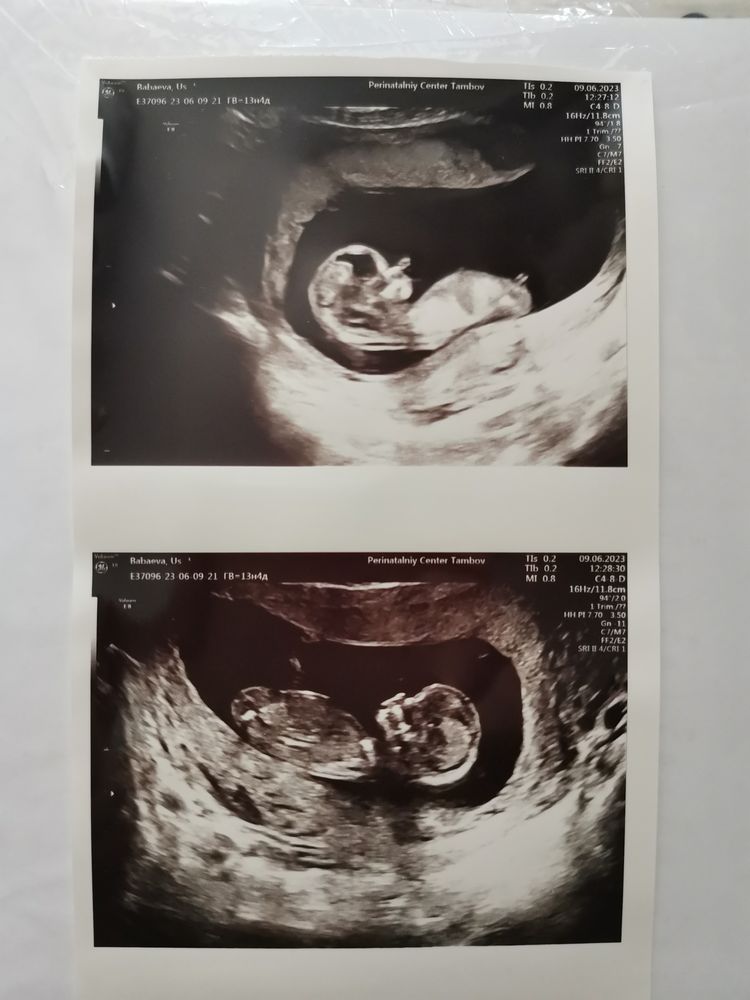

Узи почему-то заняло минуты 2 и было оно по животу, а не трансвагинальное. Я купила 3 фотографии и ушла счастливая)) По результатам УЗИ все в норме, вчера я ходила к своему гинекологу и она сказала, что кровь тоже в порядке, можно выдохнуть. Также вчера сдала кровь на второй скрининг, хотя почитала на форуме, что его обычно назначают тем, у кого какие то проблемы с первым. Странно конечно, но раз надо, то надо... буду надеяться, что все будет хорошо))